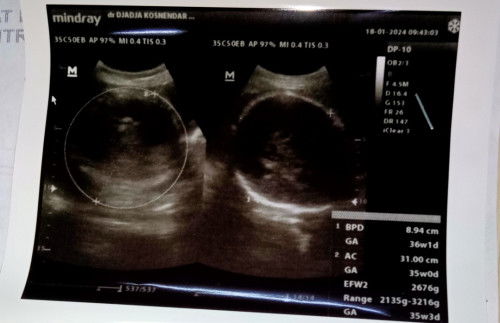

Hasil usg

Ini yang bner yang mana ya UK 36w1d apa yang 35w3d

yg pertama uk menurut lingkar kepala janin yg ke 2 uk menurut panjang janin kalau uk sesungguhnya pakai patokan usg waktu TM 1 atau bisa jg pakai hpht kalau mens nya teratur